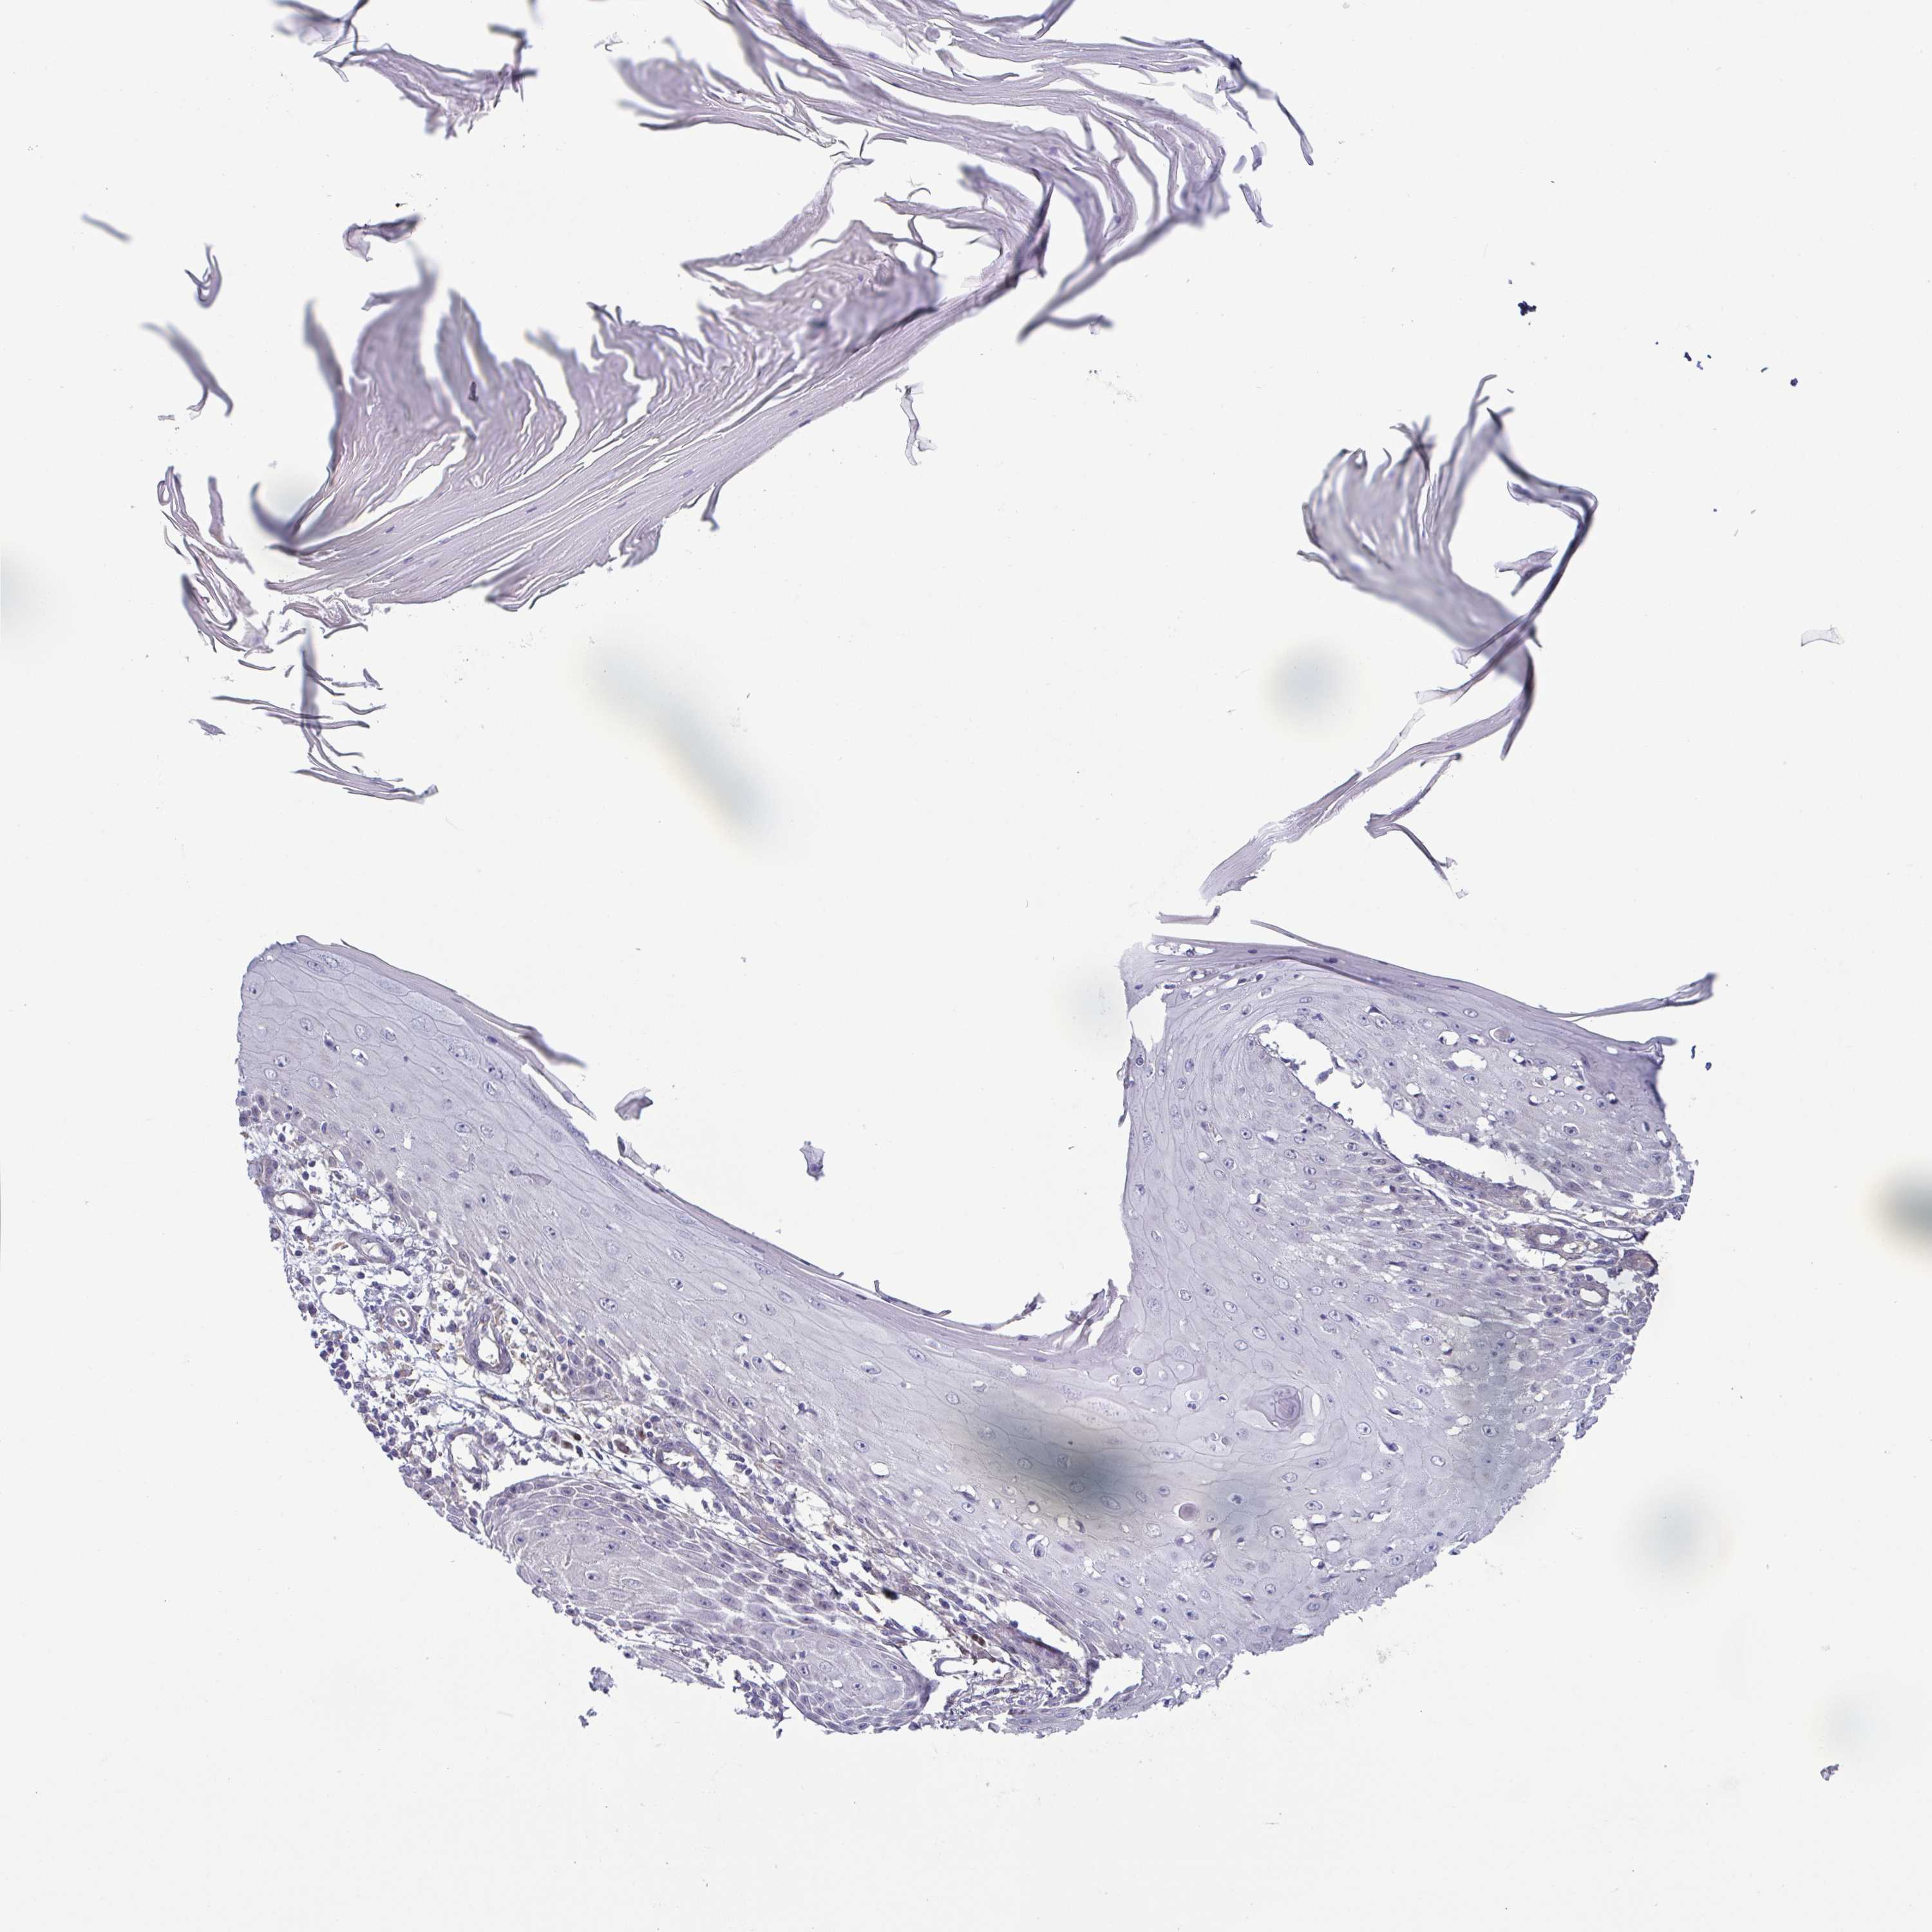

CANCER SKIN CANCER Show tissue menu

Basal cell and squamous cell cancer

SKIN CANCER - Protein expressioni

A mouse-over function shows sample information and annotation data. Click on an image to view it in a full screen mode. Samples can be filtered based on level of antibody staining by selecting one or several of the following categories: high, medium, low and not detected. The assay and annotation is described here.

Each image is clickable and will lead to virtual microscopy that enables deeper exploration of all samples and also displays staining intensity scores, fraction scores and subcellular localization as well as patient and tissue information for each sample.

Antibody HPA063368

Staining

High

Medium

Low

Not detected

Intensity

Strong

Moderate

Weak

Negative

Quantity

>75%

75%-25%

<25%

None

Location

Nuclear

Cytoplasmic/membranous

Cytoplasmic/membranous,nuclear

Basal cell carcinoma

BCC, high aggressive

Squamous cell carcinoma, NOS